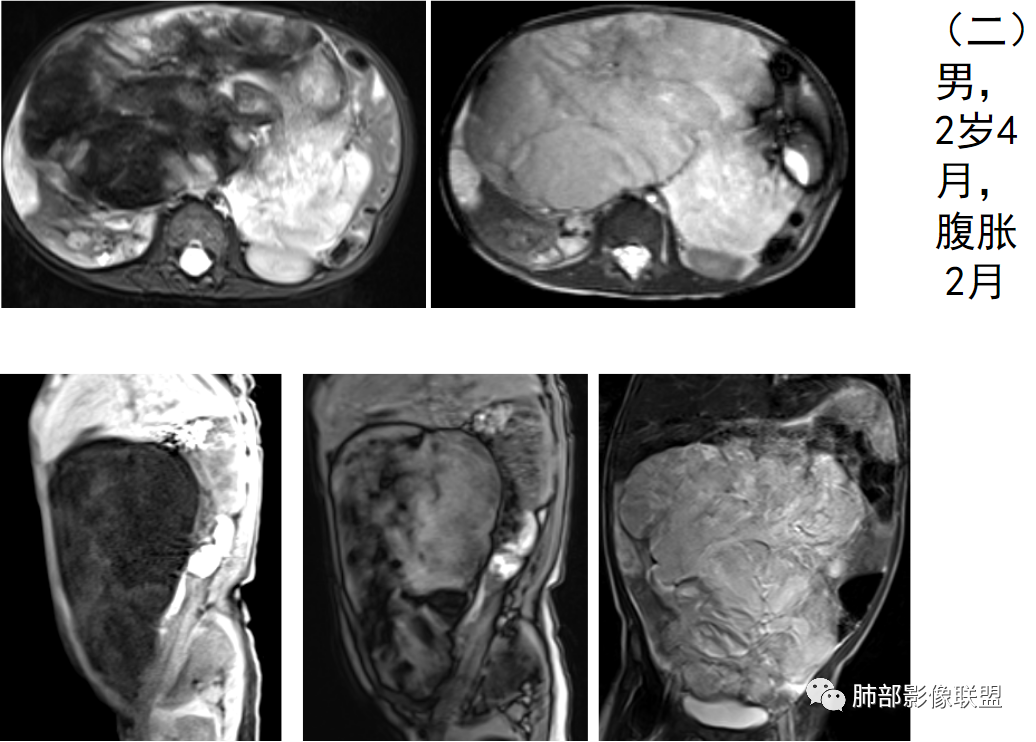

1958年由Vellios等首先报道,仅见于婴儿和年幼儿童,又称为胎儿脂肪瘤、胎儿脂肪肿瘤、胎儿细胞脂肪瘤、胚胎性脂肪瘤、先天性脂肪瘤样肿瘤不同于绝大多数的“母细胞瘤”,脂肪母细胞瘤是一种少见的幼儿软组织良性肿瘤,由不成熟脂肪细胞的异常增生形成。多发生于3岁以下儿童,约占80-90%,且男性多于女性,主要表现为无痛性肿块,有文献报道脂肪母细胞瘤发生于四肢的比例可达70%,下肢较上肢多见。也可见于头颈部、躯干、纵隔、腹膜后、肠系膜、骶尾部、阴囊、宫颈及心脏等处。该疾病的病因及发病机制尚不明确,许多文献认为可能是某些基因的突变所致,但目前尚无有力证据证明。其治疗以手术切除为主,预后较好,暂无恶变及转移的报道,但可复发。总体来说,对于其生物学行为的认识很重要,因为脂肪母细胞瘤的生物学行为属良性,应避免不必要的过度治疗。

脂肪母细胞瘤由成熟程度不同的脂肪组织、纤维间隔、黏液基质、小血管丛等间质成分组成,以脂肪组织与黏液样基质为主,其影像学表现取决于上述组织成分。典型的CT和MRI表现为:前后纵隔均可发生,常见于前纵隔;肿块大小不一,直径多在3cm~7cm,密度均匀,CT值呈水样或脂肪密度,脂肪组织密度或信号为主的肿块,其内密度或信号不均匀,可见粗细不一的分隔影,且有结节、片状影,后者可呈轻中度强化;结节状肿瘤包膜完整;弥漫性者包膜不明显,常呈浸润性生长;周围结构为受压和推移改变,可有少量胸腔积液,淋巴结无增大。

9、病例赏析